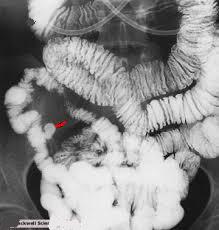

Aspect

radiologique de diverticule de Meckel .Image de

sacculaire en connexion avec la grele et extension

vers ombilique . . |

Diverticule de Meckel est une type de

diverticule de l'intestin grele , presente par la persistance

du canal omphalo-mesenterique et se voyait de 2% a 3%

dans population . Image radiologique de transit baryte

du Meckel diverticule est

image tubulaire , borgne en connexion avec grele et

extention vers ombilique . Image TDM de diverticule de

Meckel est image tubulaire de

air -liquide ,de liquide a paroi epaissie et parfois

en association image d'inflamatoire peripherique

| Aspect d'une diverticule de Meckel

avec image en tubulaire borgne sur le bord

antimesenterique de ileon , se voyait si net sur

technique enteroclyse baryte de

l'intestin |

Diverticule de Meckel : Image

en tubulaire , borgne en connexion du grele au bord

antimesenterique de ileon et extension vers

l'abdomen .( fleche rouge ) |